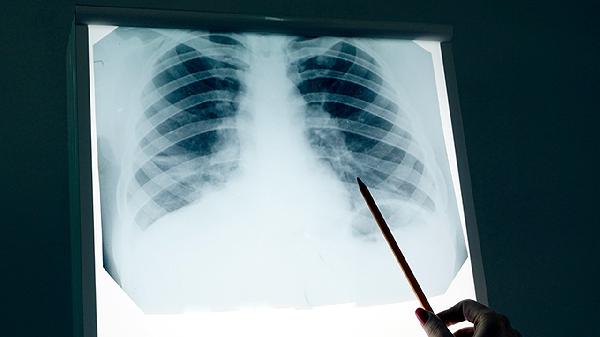

有没有肺气肿,看睡觉就知?医生:肺气肿患者,睡觉时或有4异常

凌晨三点,老李又一次被自己的咳嗽惊醒,胸口像压了块大石头,呼吸时总感觉"气不够用"。这种夜不能寐的日子已经持续了半年,直到体检才发现——肺气肿早已悄悄找上门。其实,肺气肿这个"沉默的杀手"在夜间最容易露出马脚,只是很多人把异常当成了"年纪大了的正常现象"。